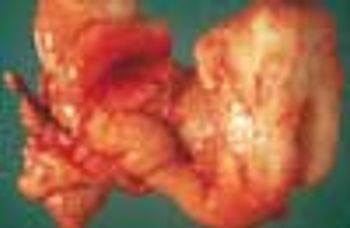

A 7-year-old boy presented with two testicles on the left side of the scrotum. The superior one was half the size of the inferior one, which measured 2 × 1 cm. The testicle on the right side measured 2 × 1 cm. Surgical exploration was done, and the atrophic left supernumerary testicle shown in the photo was removed. Biopsy specimens taken from the remaining testicle were normal.